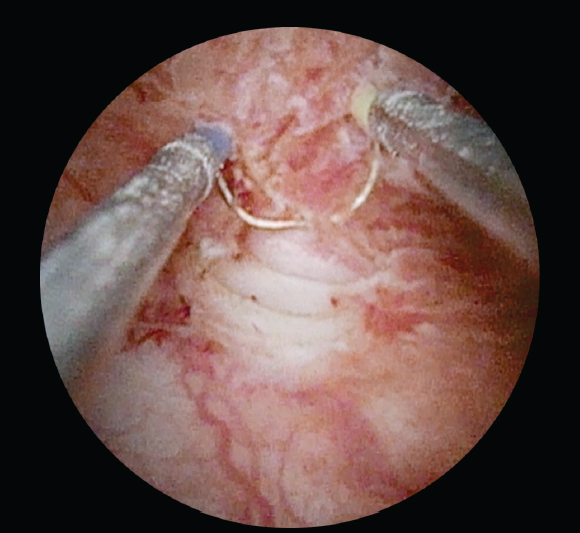

В группу 1 было включено 49 пациентов (средний возраст 62,4 ± 9,0 года), всем больным выполняли классическую ТУРМП с последующим внутрипузырным введением химиопрепарата. Группу 2 составили 48 пациентов (средний возраст 57,7 ± 11,2 года), подвергшихся ТУРМП с последующей Nd:YAG-лазерной абляцией ложа опухоли и введением химиопрепарата в послеоперационном периоде. Оперативные вмешательства проводили под спинальной анестезией. Хирургический этап лечения включал диагностическую уретроцистоскопию, позволяющую оценить состояние мочеиспускательного канала, шейки и слизистой оболочки мочевого пузыря, расположение устьев мочеточников, количество и объем образований. Следующим этапом было выполнение резекции стенки мочевого пузыря с опухолью до мышечной оболочки: использовалась как резекция единым блоком, так и стандартная ТУРМП с использованием различных источников энергии (рис. 1). Заключительный этап — гемостаз различными источниками энергии (биполярная, лазерная), а также абляция ложа опухоли Nd:YAG-лазером у пациентов группы 2 (рис. 2).

Рис. 1. Этап трансуретральной резекции стенки мочевого пузыря с опухолью

Fig. 1. Transurethral resection of the bladder wall tumor